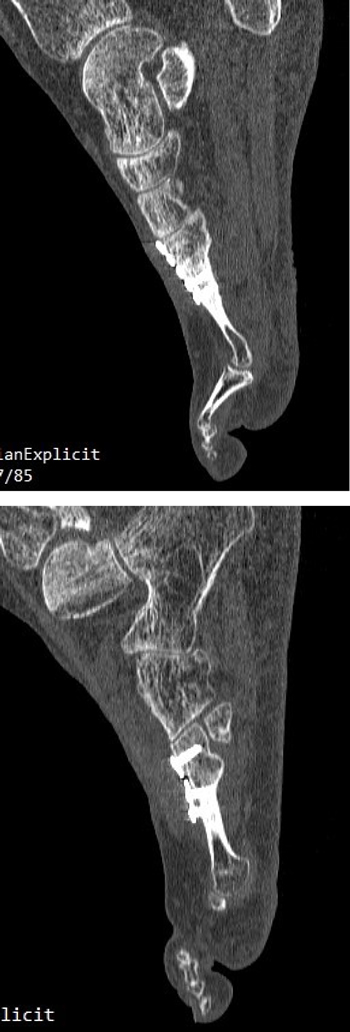

Se realizó radiografía dorso-plantar en carga del pie derecho (Figura 1) que mostraba una imagen radiológica compatible con ausencia de consolidación de las osteotomías en las bases de 2.º, 3.º y 4.º metatarsianos, además de la presencia de hallux abductus valgus. Se solicitó una tomografía axial computarizada (TAC) para estudiar más detenidamente el estado actual del proceso de consolidación ósea. La paciente acudió con resultado de TAC el 5 de mayo de 2015, donde se evidenció la ausencia completa de consolidación ósea en segundo metatarsiano (Figuras 2A y 2B), consolidación prácticamente completa de tercer metatarsiano (Figura 2C) y la presencia de callo óseo con consolidación incompleta en el cuatro metatarsiano (Figura 2D).

Figura 2. Radiografía dorso-plantar en carga del pie derecho. Se evidencia la ausencia de consolidación de las osteotomías en las bases de 2.º, 3.º y 4.º metatarsianos después de 9 meses de la intervención inicial.

Imagen 6. TAC postoperatorio a los 5 meses. 6A. Imagen del 2º metatarsiano que muestra integración del injerto con la placa dorsal. 6B. Imagen del 4º metatarsiano que muestra consolidación del 4º metatarsiano.